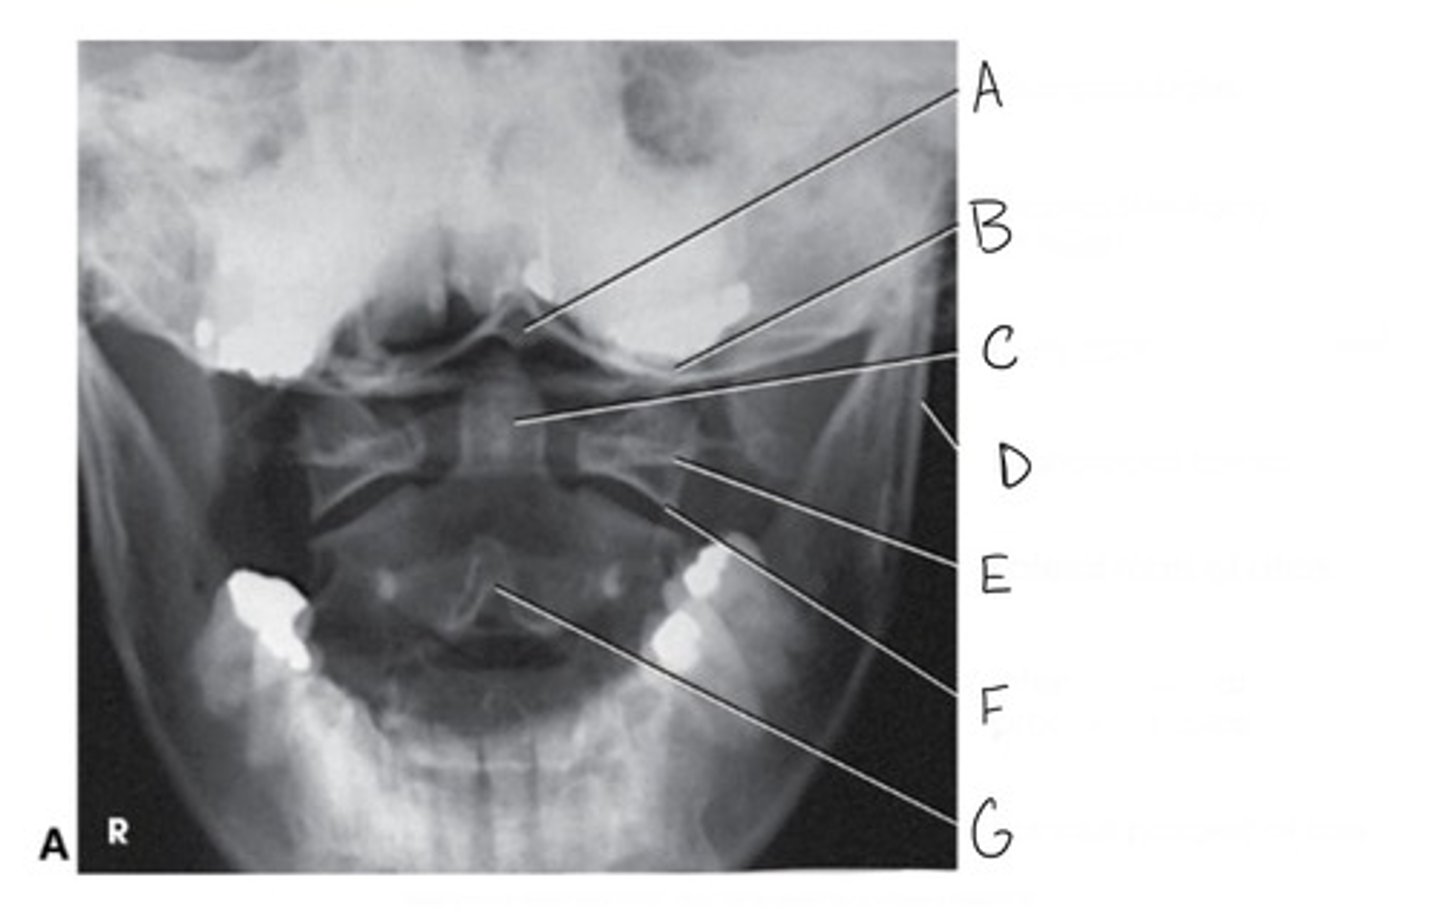

Zygapophyseal joint

What is A?

Intervertebral foramina

What are B?

Transverse foramina

What are C?